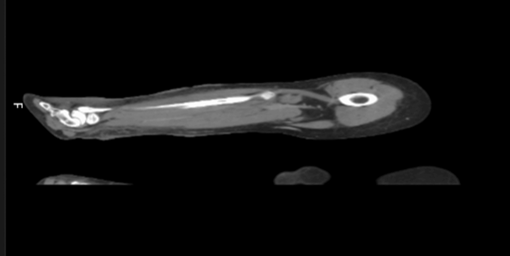

Cultures remained negative, and broad-spectrum

antibiotics were administered. A ct scan ruled out nf, showing infection

confined to subcutaneous tissue without fascial involvement, specifically

absence of deep plane infiltration, emphysema or organized collections (figure 2).

Figure 2:

ct scan of right leg Signs of subcutaneous

tissue densification without collections or deep-tissue gas formation